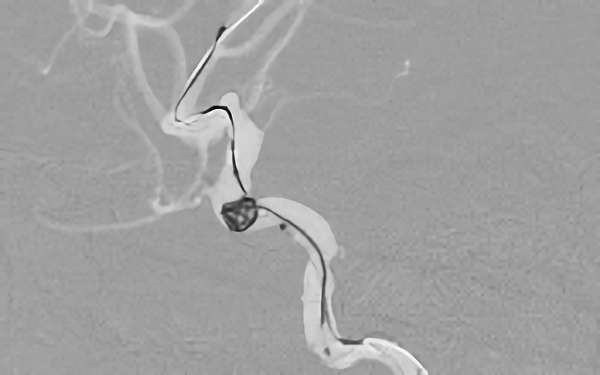

'26年4月

左後下小脳動脈瘤

80代

大阪府の病院

No.1631 手術前

No.1631 手術中

No.1631 手術後